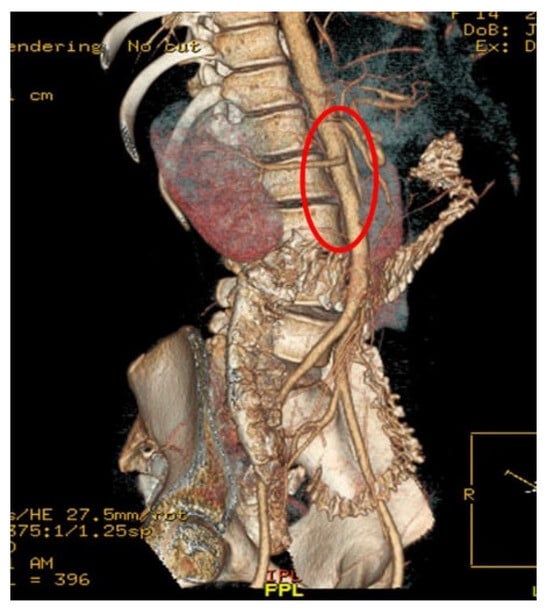

Ureteral and Vascular Events During Robotic Post-Chemotherapy Retroperitoneal Lymph Node Dissection: Technical Insights and Management Considerations

by Manuel Saavedra Centeno, Eduardo Albers Acosta, Clara Velasco Balanza, Lira Pelari Mici, Carlos Márquez Güemez, Marta Pérez Pérez, Ana Sánchez Ramírez and Luis Alberto San José Manso

Complications 2026, 3(1), 1; https://doi.org/10.3390/complications3010001 - 8 Jan 2026

Robotic retroperitoneal lymph node dissection (R-RPLND) represents an evolution in the surgical management of testicular germ cell tumors, offering reduced morbidity compared with open approaches. However, this procedure remains technically challenging, particularly after chemotherapy, due to dense fibrosis and distortion of the retroperitoneal [...] Read more.

Robotic retroperitoneal lymph node dissection (R-RPLND) represents an evolution in the surgical management of testicular germ cell tumors, offering reduced morbidity compared with open approaches. However, this procedure remains technically challenging, particularly after chemotherapy, due to dense fibrosis and distortion of the retroperitoneal anatomy. We report a case of an unrecognized intraoperative thermal injury causing a partial transection of the proximal ureter presenting postoperatively as a urinary fistula following R-RPLND for residual mass resection, along with a focused review of the contemporary literature on procedure-related complications. A review of large series highlights severe complications (Clavien–Dindo ≥ III) occurring in 6–12% of cases, with ureteral injuries occurring in up to 6%, often identified after surgery. This case underscores the importance of meticulous dissection, awareness of altered anatomy, and prompt intervention when unexpected events arise during R-RPLND. Full article

Show Figures